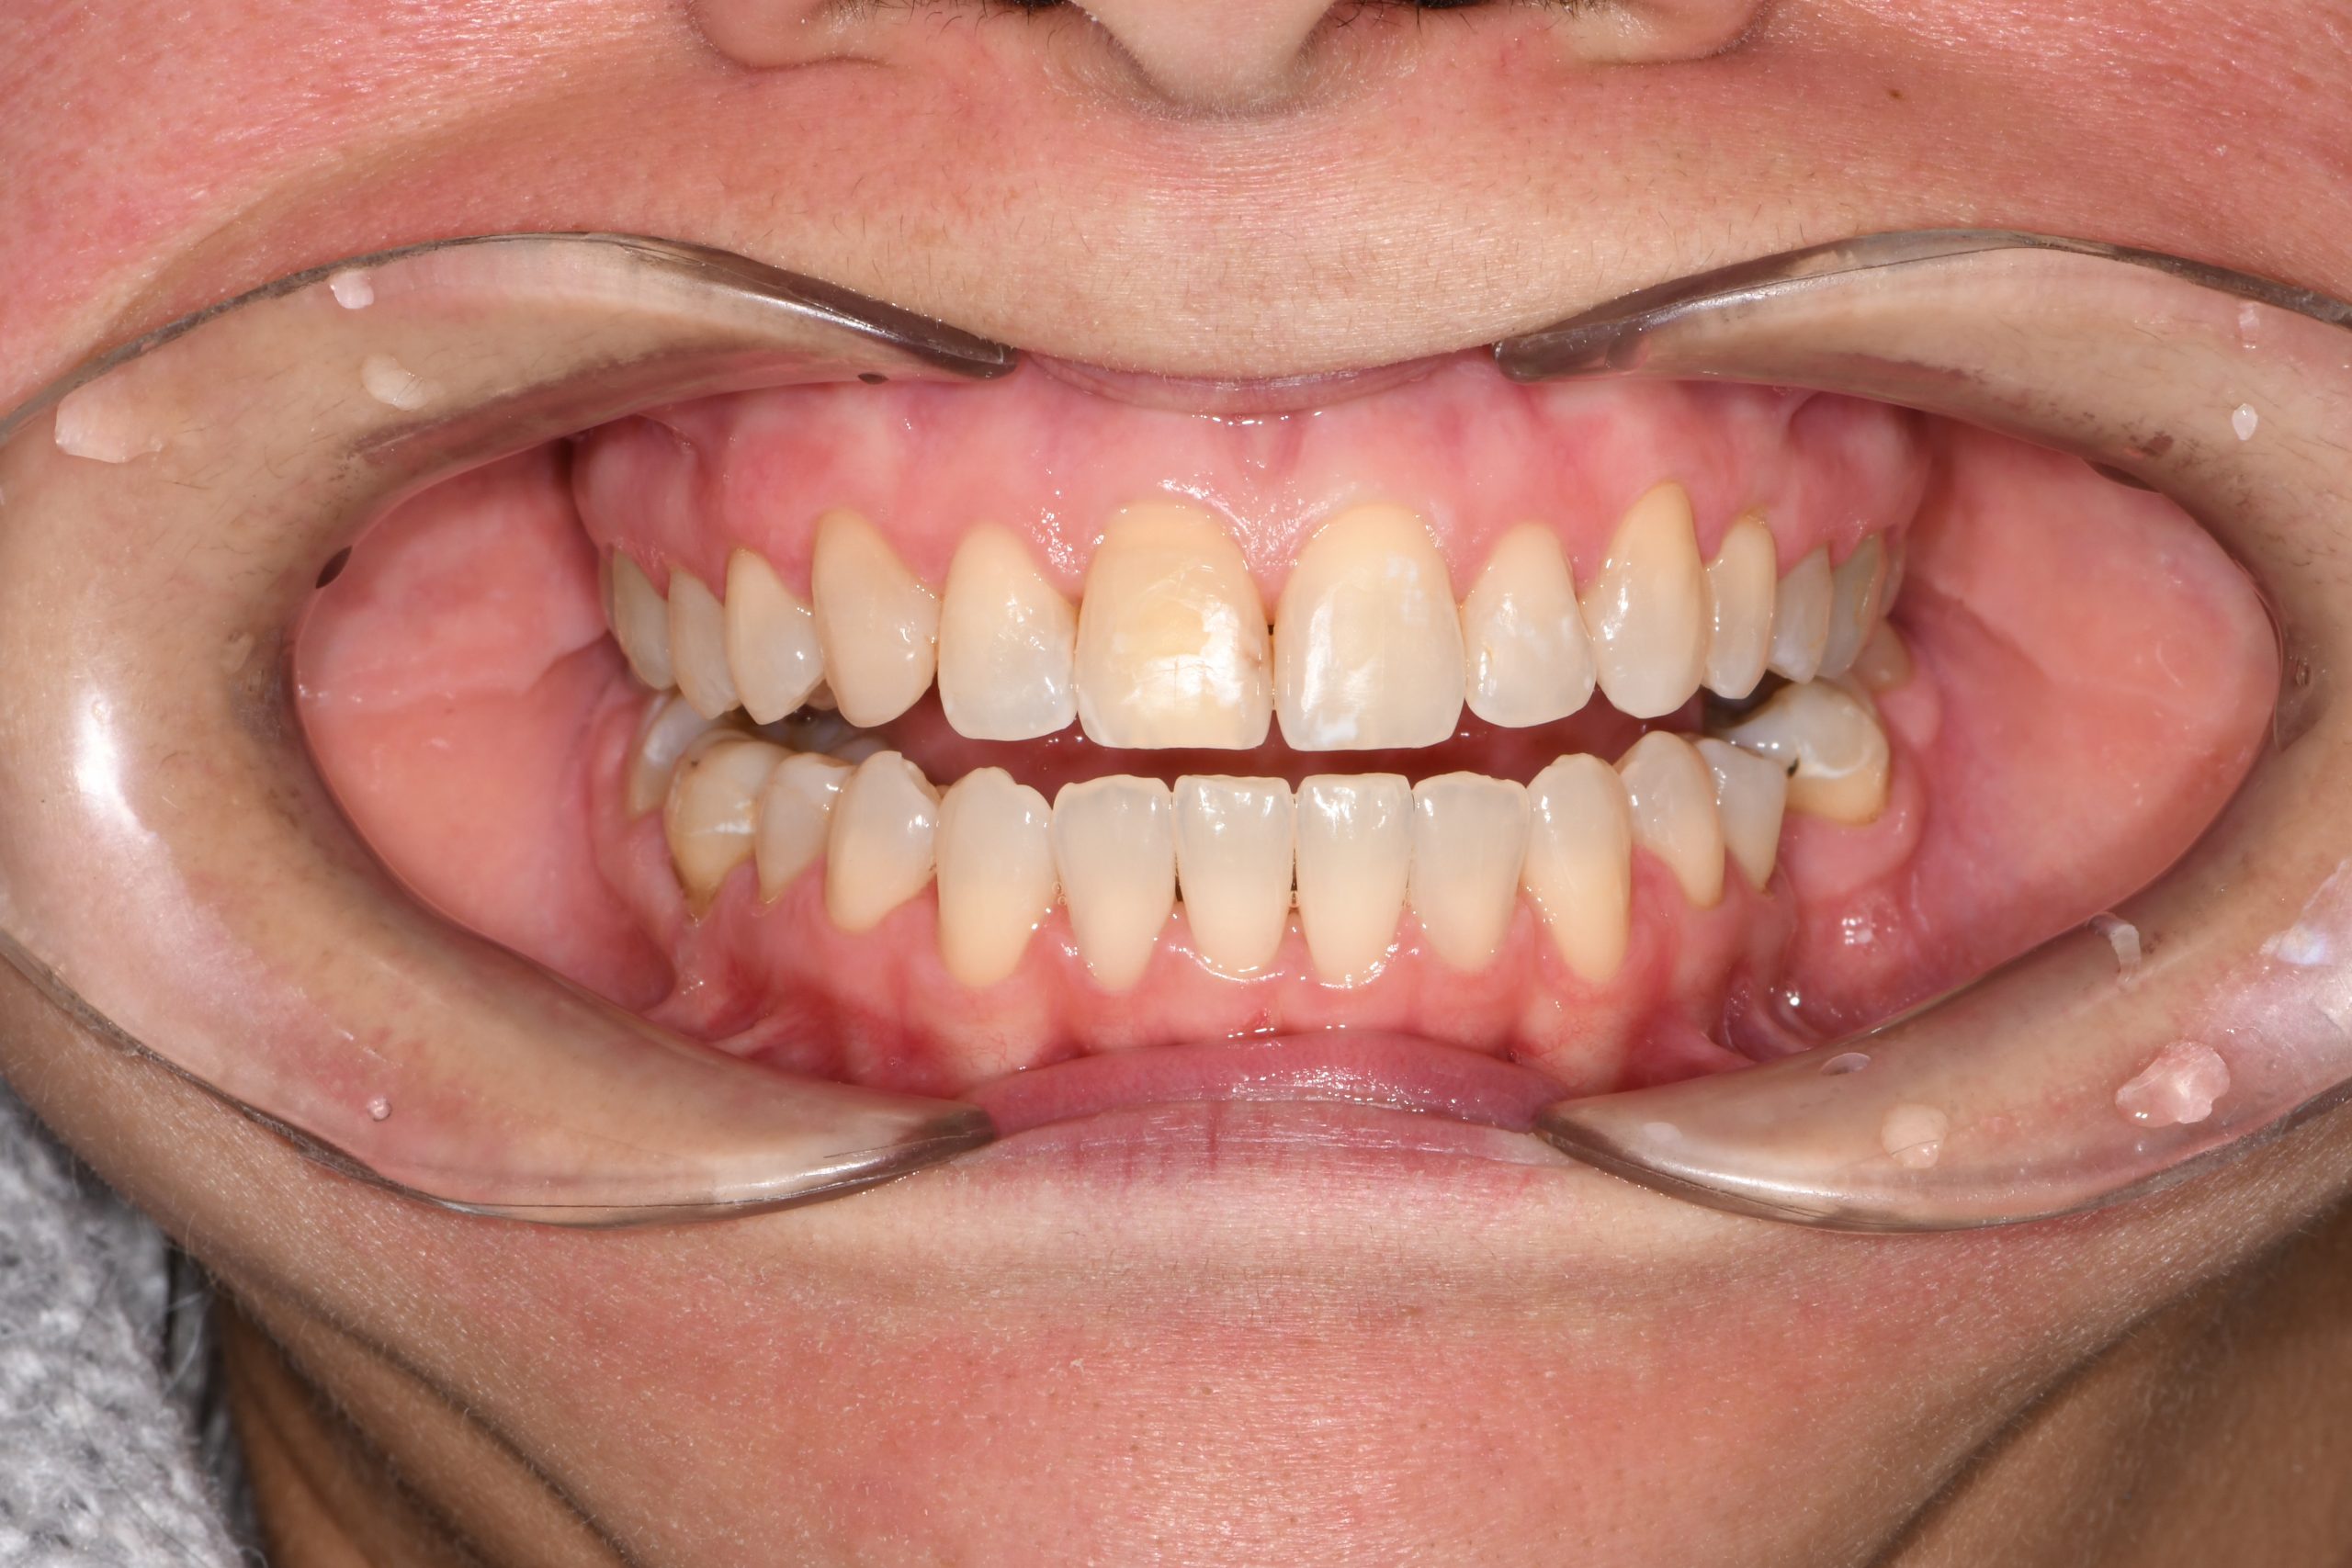

Az elmúlt évekből rengeteg szakmai referenciát tudnánk bemutatni, amelyek különböző fogszabályozási problémákat oldottak meg. Válogatva a több száz esetből, ezen az oldalon olyan képeket, információkat igyekeztünk bemutatni, amelyeknek a segítségével a jövőbeni pácienseinknek azt tudjuk üzenni: A Te fogsorod is lehet gyönyörű!

(Képeket a Pácienseink külön írásos beleegyezésével mutatjuk be!)